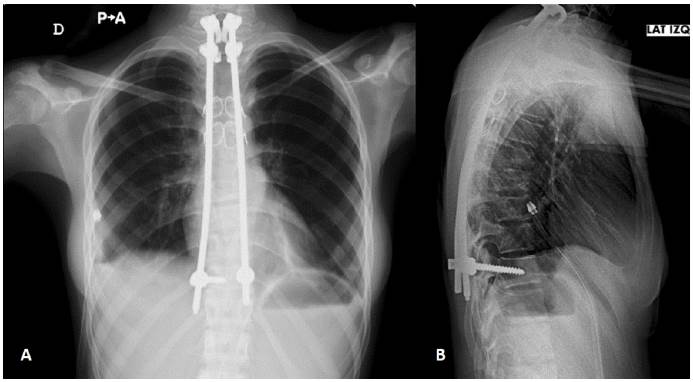

En el postoperatorio inmediato la paciente presenta disnea y tos, con matidez a la percusión y abolición de murmullo vesicular de hemitórax derecho, con lo que se plantea derrame pleural que ameritó colocación de tubo de tórax, evidenciando la presencia de exudado lechoso, fue valorada por servicio de neumología quien indica iniciar tratamiento con rifampicina, etambutol e isoniazida. El estudio de rayos X de tórax post-toracotomía muestra derrame pleural y presencia de la instrumentación (Figura 4).

Figura 4 Radiografía de anteroposterior (A) y lateral (B) de tórax posoperatoria. Observe la disposición del material de osteosíntesis.